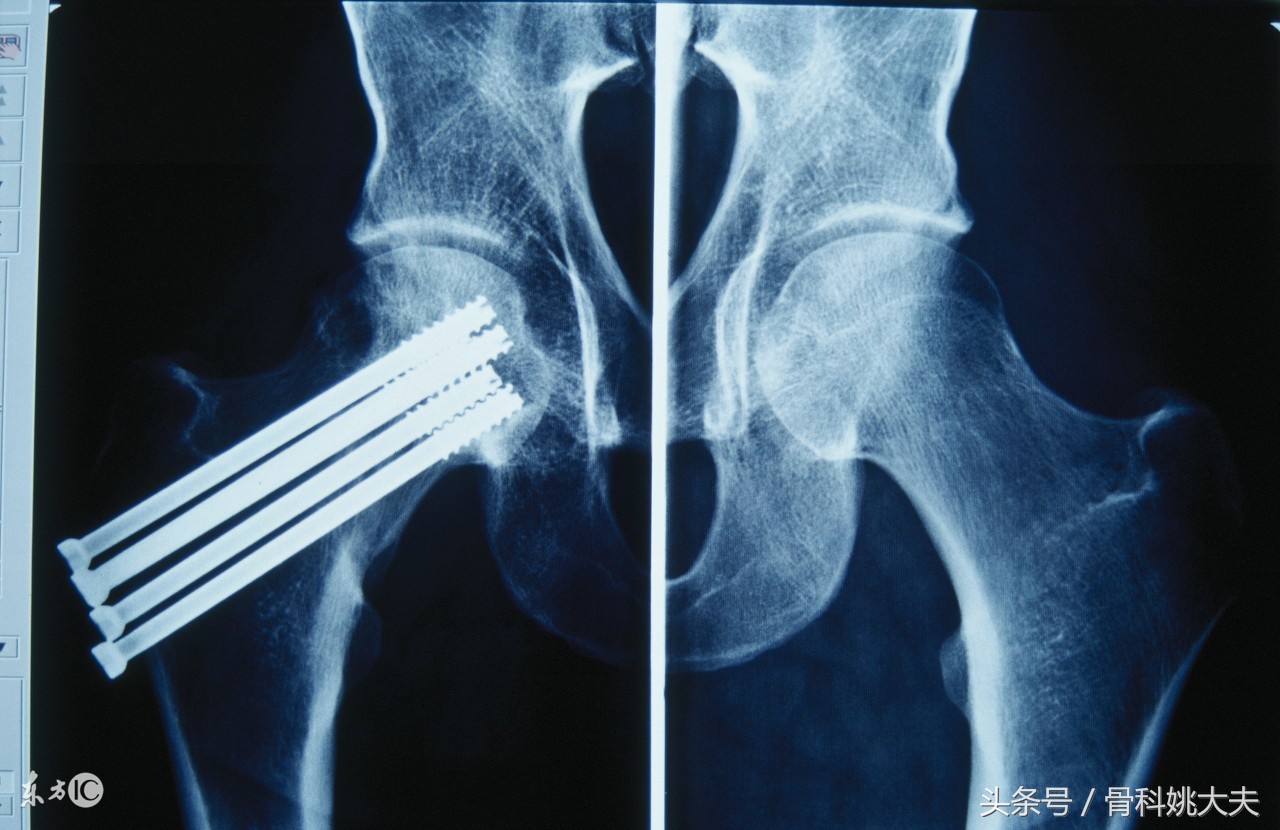

5.骨折部位 肱骨中下1/3,胫骨中下1/3 股骨颈骨折 舟骨骨折,距骨颈骨折等部位骨折愈合困难

4.手术操作的影响剥离过广影响骨折愈合。微创或闭合复位髓内针固定愈合较快,但这种方式复位一般较差。所以手术方式各有各的优势和缺点,具体执行要听主刀医生的意见,因为骨折类型,软组织情况以及技能熟练程度,手术设备和条件决定着内固定的方式。过多的干扰医生的判断受苦的只能是自己。